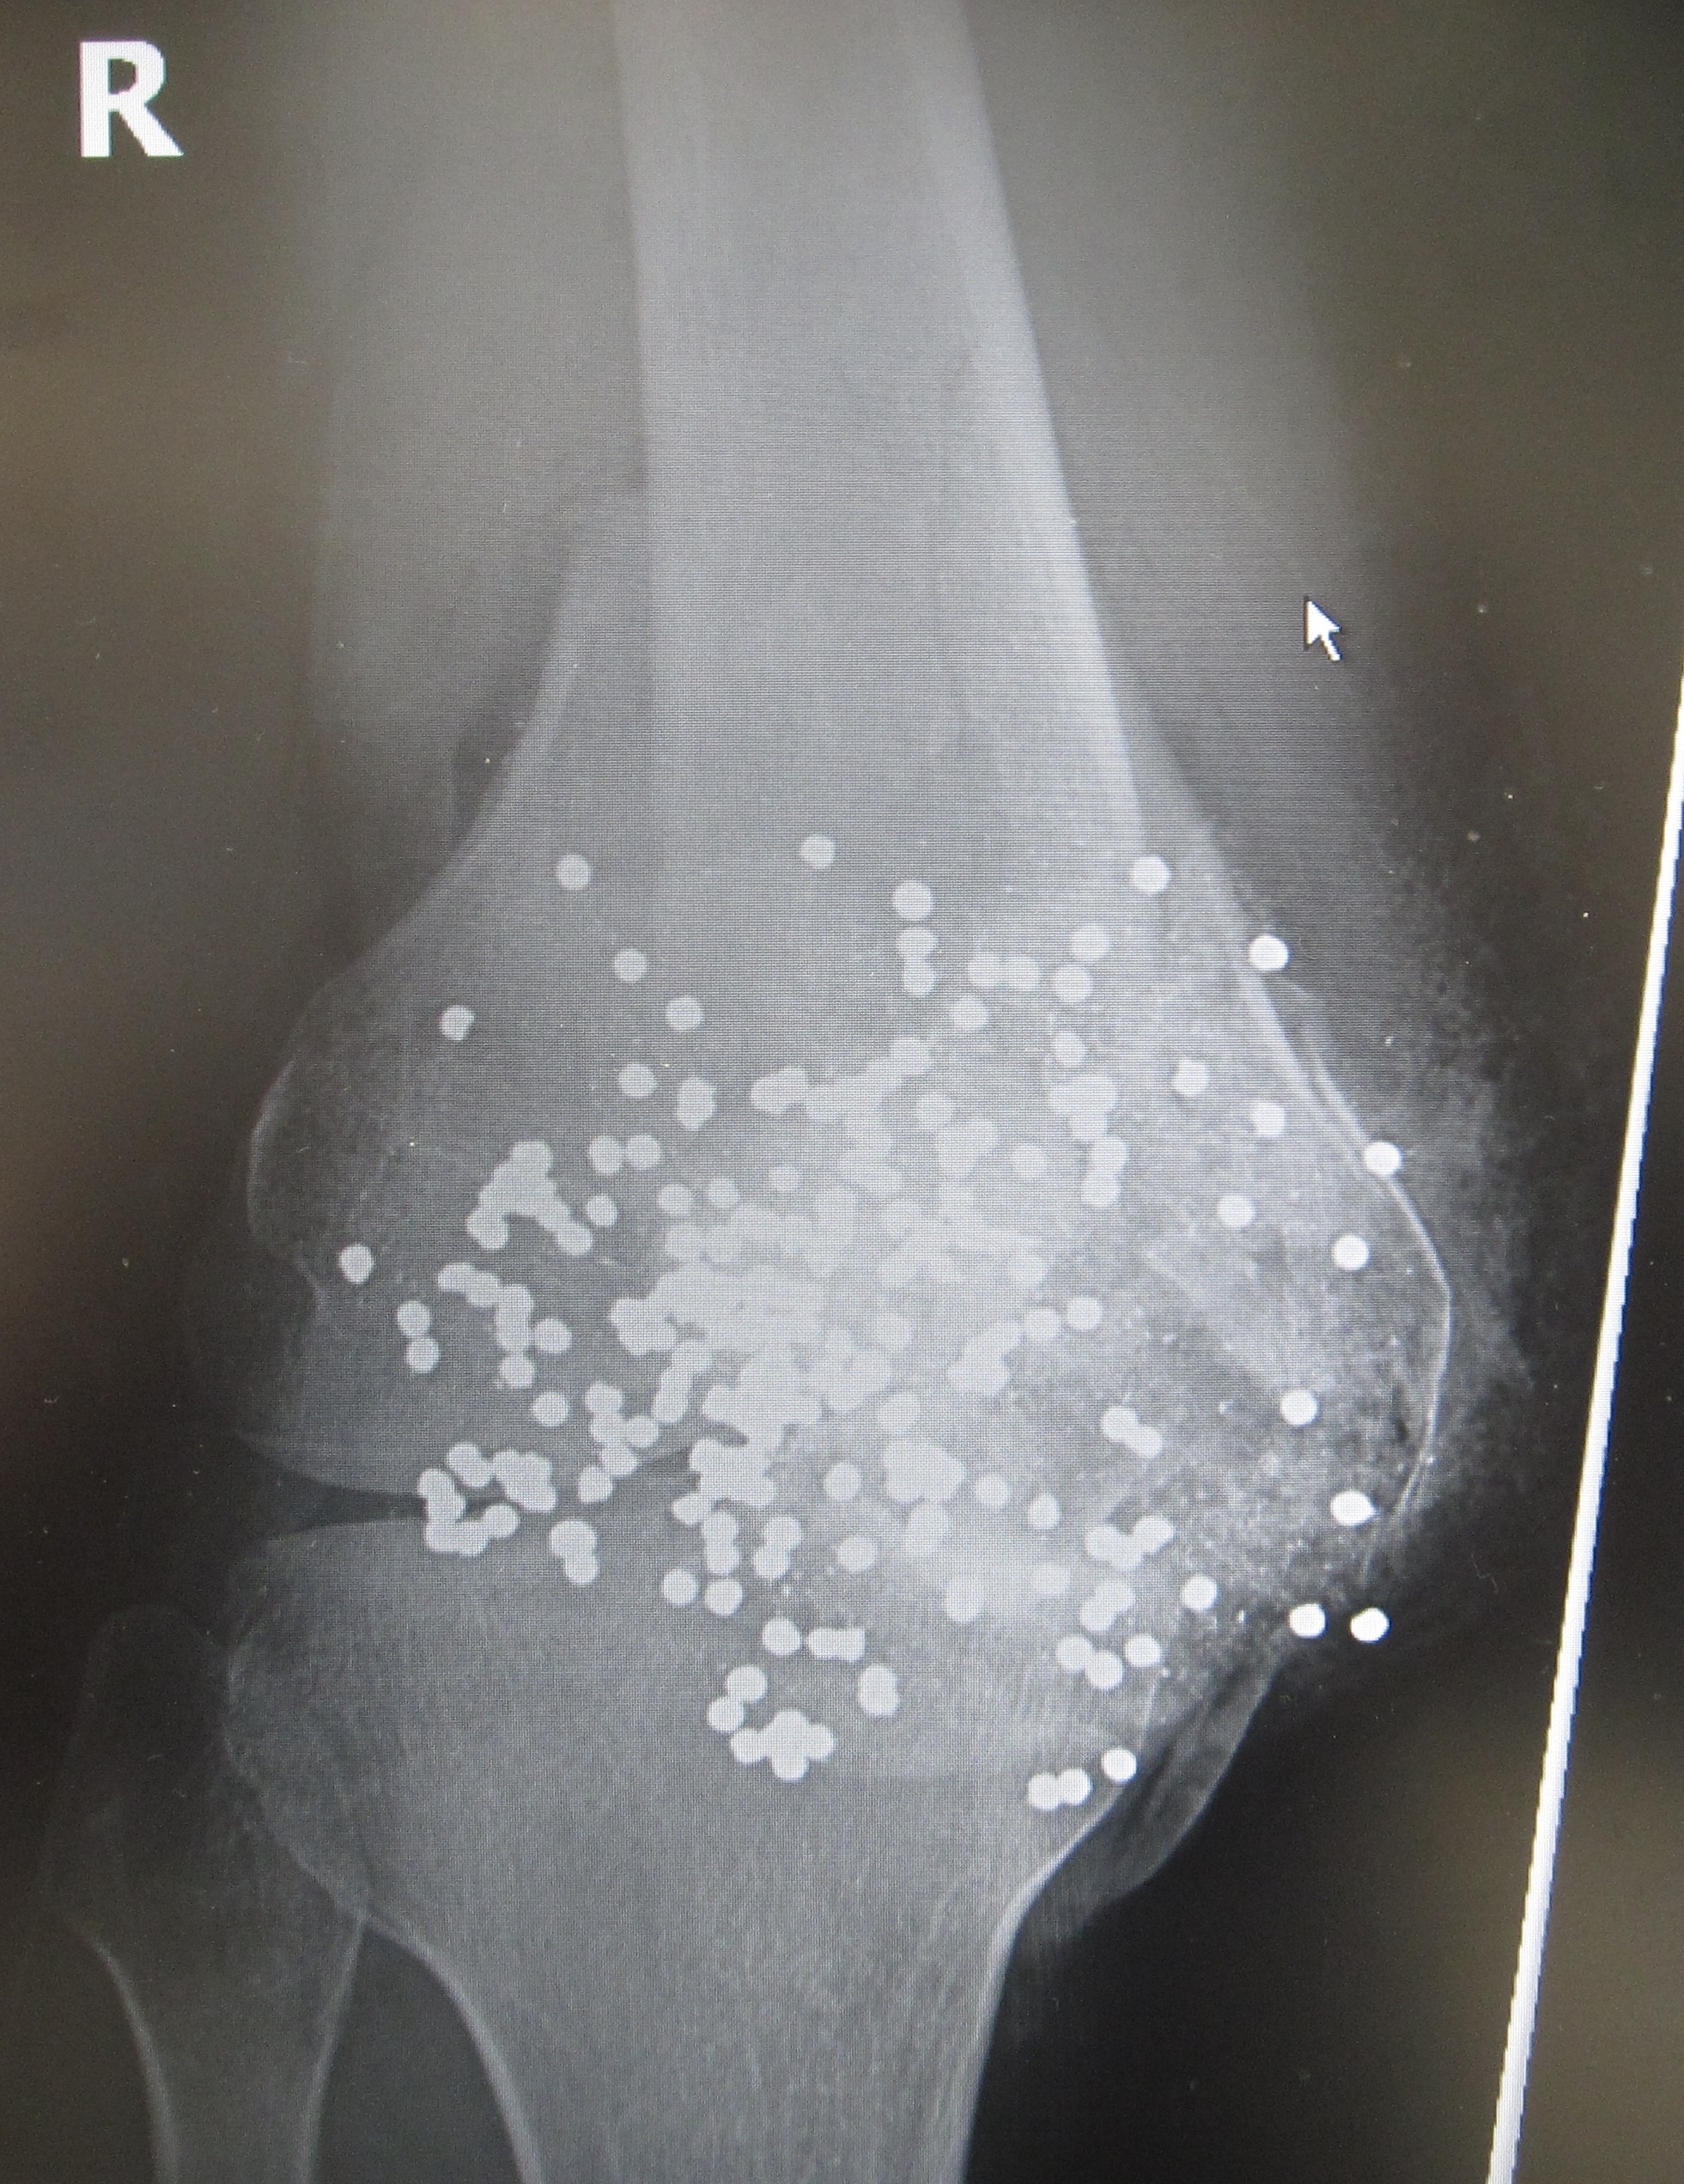

무릎에 근접 거리에서 산탄총으로 인한 부상의 방사선 사진. 산탄총 펠릿이 파편화된 슬개골, 원위 대퇴골 및 근위 경골 내부에 보입니다.

무릎에 근접 거리에서 산탄총 폭발 부상의 방사선 사진. 버드샷 펠릿이 파편화된 슬개골, 원위 대퇴골 및 근위 경골 내부에 보입니다.